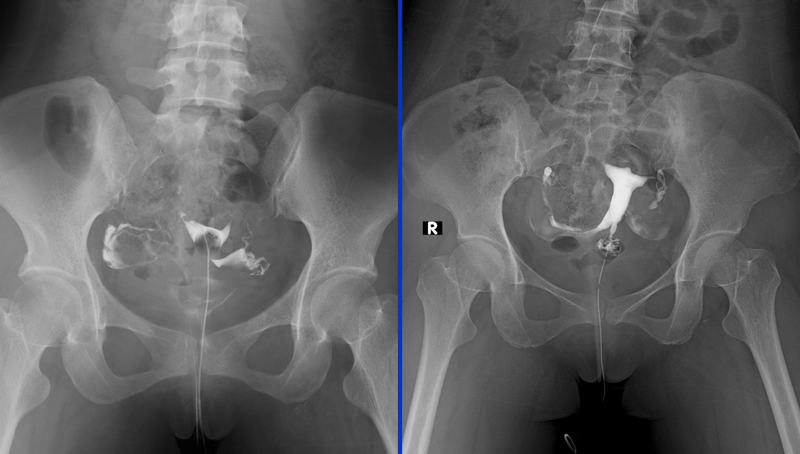

Chụp HSG là gì? Chụp HSG (Hysterosalpingography) là một phương pháp chẩn đoán hình ảnh dùng để kiểm tra tình trạng của tử cung và vòi trứng, hai bộ phận quan trọng trong hệ thống sinh sản nữ. Trong quá trình thực hiện chụp HSG, bác sĩ sẽ sử dụng tia X và một chất cản quang để tạo ra hình ảnh chi tiết về các cơ quan này. Mục đích của phương pháp này là phát hiện các vấn đề về cấu trúc hoặc chức năng của tử cung và vòi trứng, như tắc nghẽn vòi trứng, dị dạng tử cung, hoặc các khối u, polyp trong tử cung.

Chất cản quang sẽ được tiêm qua cổ tử cung vào trong tử cung và vòi trứng. Chất này sẽ lan tỏa qua tử cung và các vòi trứng, sau đó bác sĩ sẽ tiến hành chụp X-quang. Qua hình ảnh X-quang, bác sĩ có thể quan sát được sự thông thoáng của vòi trứng và cấu trúc của tử cung.